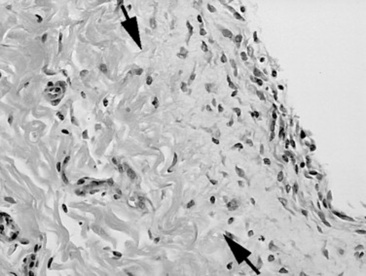

As healing progresses, fibroblasts migrate into the fibrin and a layer of granulation tissue forms both beneath and on top of the original basement membrane (Fig. 32-39). Mesothelial cells produce connective tissue growth factor in response to IL-1β, which simulates fibroblast proliferation.190 During this stage IL-1 stimulates and prostaglandin E2 inhibits fibroblast activity in the injured serosa. Primordial stem cells migrate to the surface and change to form a new mesothelium, a metaplasia likely under the control of growth factor from fibroblasts. The greater the inflammatory reaction within the serosa and on the surface, the more fibroplasia occurs, delaying mesothelium resurfacing and increasing the chance for adhesion formation or bowel scarring. Experimentally the severity of adhesions is correlated with increasing concentrations of TNF-α in peritoneal fluid, and antibodies against TNF-α can decrease adhesion formation.266,267 Healing of the serosa may not result in bowel-to-bowel adhesions but can still cause bowel and mesenteric scarring, which can cause luminal narrowing or kinking. The serosa also becomes thickened, which may result in bowel dysfunction or may interrupt the vascular supply, resulting in chronic obstruction.

Fig. 32-39 Photomicrographs of the serosa with addition of a fibrous layer extending beyond the original level of the basement membrane (arrows) 10 days after bowel ischemia and reperfusion. (Hematoxylin and eosin stain.) The new serosa surface has yet to heal with a new mesothelial layer.